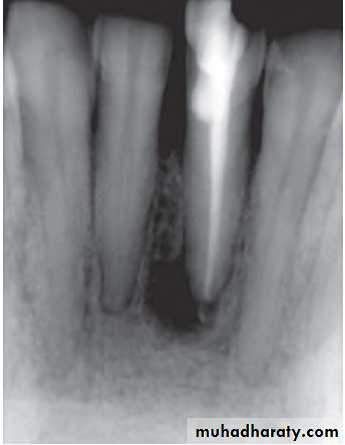

7) External root resorptionIn external root resorption, root resorption affects the cementum or dentin of the root of tooth. It can be:• Apical root resorption• Lateral root resorption• Cervical root resorption.

Etiology:

The same as internal root resorption but here it is mostly associated with trauma to the teeth that injure the cementum. Other factors include:• Infected necrotic pulp

• Over instrumentation during root canal treatment

• Trauma

• Granuloma/cyst applying excessive pressure on tooth root

• Replantation of teeth

• Adjacent impacted tooth.

• • Bleaching.

Symptoms

• Asymptomatic during development

• When root is completely resorbed, tooth becomes mobile

• When external root resorption extends to crown, it gives “Pink tooth” appearance

• When replacement resorption/ankylosis occur, tooth becomes immobile with characteristic high percussion sound

Radiographic Features

• Radiolucency at root and adjacent bone• Irregular shortening or thinning of root

• Loss of Lamina dura.

Treatment

• Remove stimulus of underlying inflammation.

• Nonsurgical endodontic treatment should be attempted before surgical treatment is initiated.